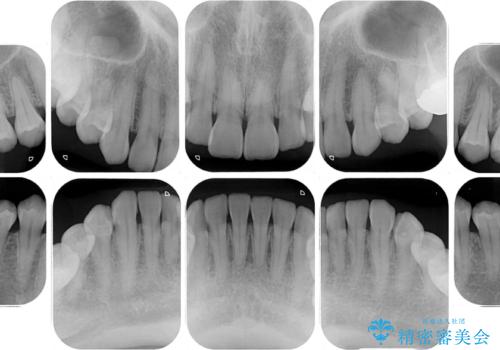

- 奥歯の銀歯をセラミックにしたいとのことで来院された患者様です。

当初は奥歯のみの治療をご希望でしたが、話を進めていくうちに、軽度ではあるものの、幼少期の薬の影響で歯が変色していることがコンプレックスであるということが分かりました。

長年歯の色が塞ぎ込んでいた部分があるとのことで、これを機会に全ての歯を真っ白にするために、オールセラミッククラウンにて補綴治療を行うこととしました。